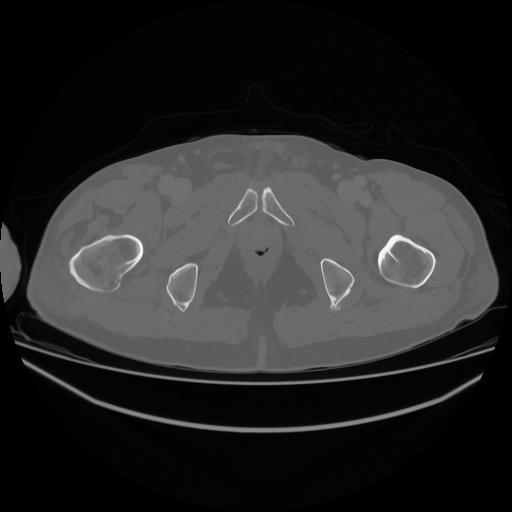

5 CUERPO,CE,Vol,1.0,CUERPO,,